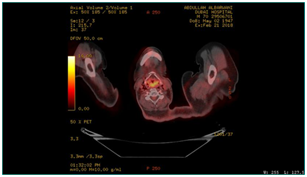

A biopsy was taken and histopathology was done using immunohistochemically markers and showed angiosarcoma, PET CT scan was performed on 21/02/2018 and showed the following: hypermetabolic suspicious lymph node in the right infraclavicular region, hypermetabolic focus in the region of the left mandible, adjusting left margin of the tongue and the hypopharynx (Figure 4–6). Patient was diagnosed before as squamous cell carcinoma of the right lateral side of the tongue.  Patient was operated in Oman on 8th November, 2006 for a white tongue lesion, and then operated again on 13th December, 2006 for tongue carcinoma. Lastly, partial Glossectomy was done for recurrent tongue carcinoma on 24th March, 2010 (Figure 7). After surgery, patient received total radiotherapy treatment of the face and neck using 6 MV photons, 2 fields and a total dose of 60Gy (44 Gy+20 Gy off cord) from 21st June, 2010 till 03rd August, 2010. Patient was then referred to a specialized center, where further management was done. This case was reported to high light an infrequent long-term complication of radiotherapy.

Figure 4 PET CT scan, showing hypermetabolic focus at the hypopharyx, post cricoid area.

Figure 5 PET CT scan, showing hypermetabolic focus at the region of left mandible, adjusting left margin of the tongue.

Figure 6 PET CT, showing hypermetabolic suspicious lymph node in the right infraclavicular region, hypermetabolic focus in the region of left mandible.